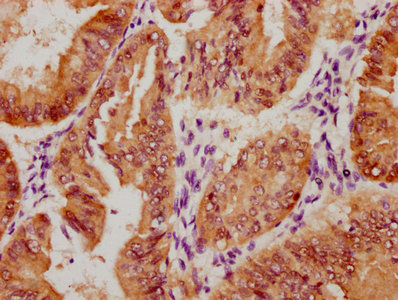

The image on the left is immunohistochemistry of paraffin-embedded Human brain tissue using CSB-PA196653(ABI1 Antibody) at dilution 1/40, on the right is treated with synthetic peptide. (Original magnification: ×200)